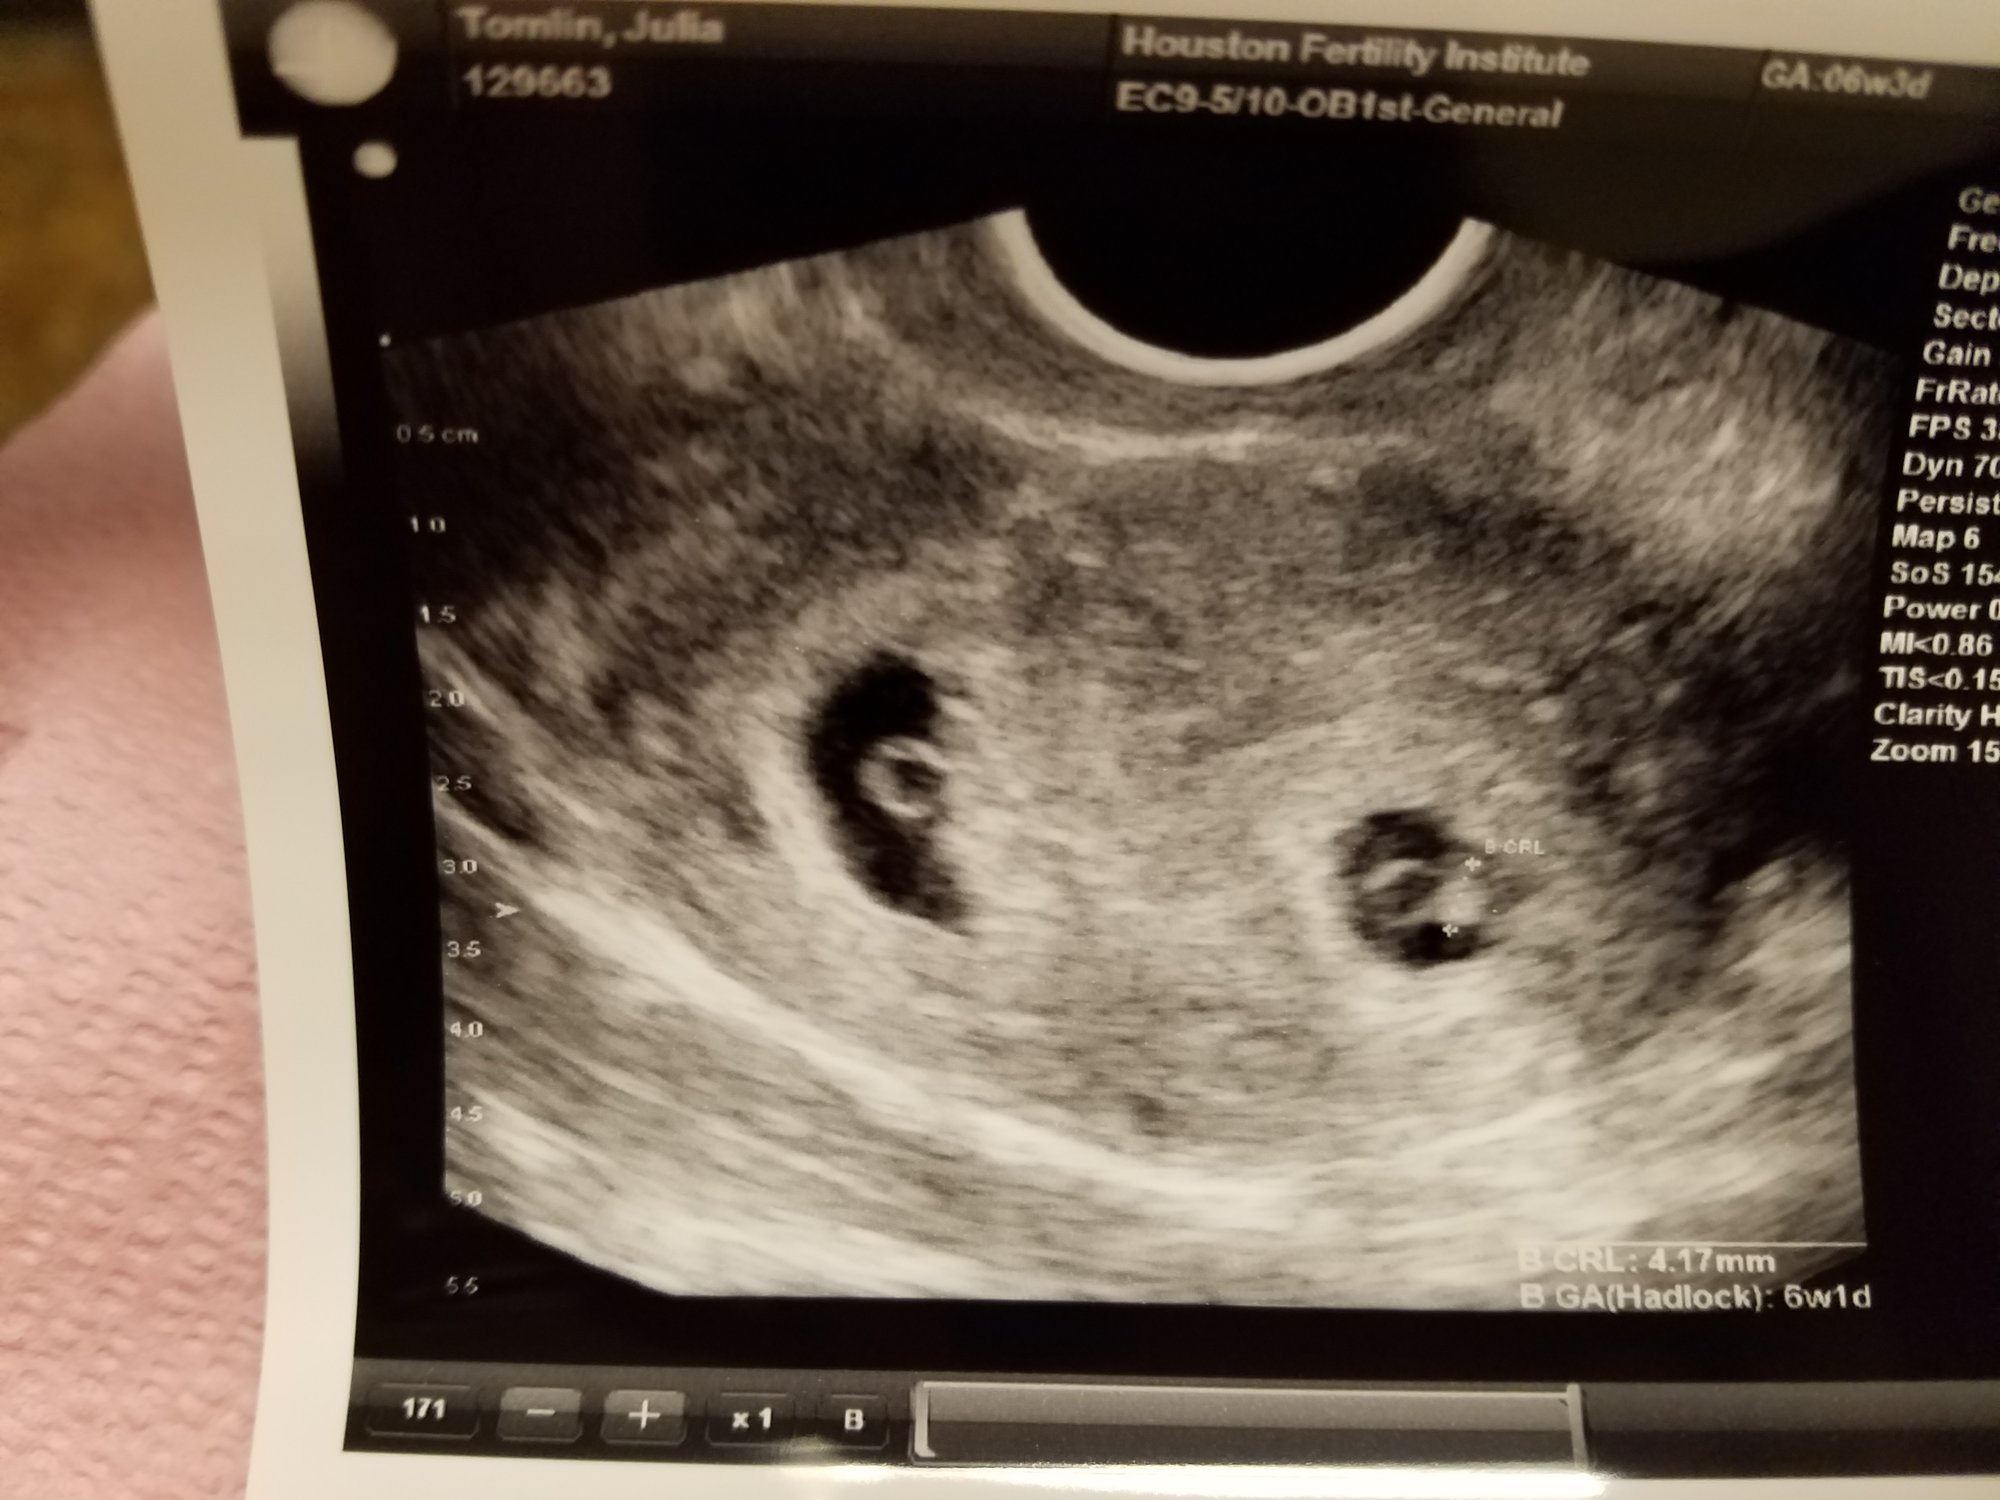

Had my first US today and found out we're having twins! Got to see them and hear both heartbeats. Dr said heart rate is perfect and they are measuring fine

1. How far along are you? 6 weeks 4 days What is your EDD? August 4th  ( Found this out yesterday, my calculations were off by 3 days)

2. Which oh-so-lovely pregnancy symptoms are you having? none! Which had me freaking out yesterday. I told the Dr that as well right before my ultrasound. He said "Don't feel cheated, feel fortunate." I was so sure the screen was going to show nothing.... because I feel so good. I was thrilled when we saw/heard both sweet babies.

3. When is your next appointment?  12/26/16

4. Anything else you'd like to share? The fact that we're having twins is still blowing my mind. I knew there was a chance with us putting in two but the reality that they both stuck is still just surreal. We are on cloud 9. Waiting for it all to sink in and then I'm sure I'll be freaking out about all that we need to do to get prepared for them.